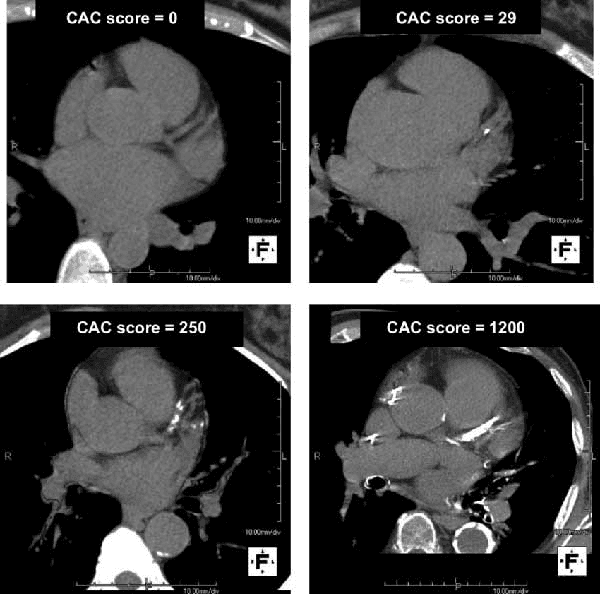

Emerging biologic tools allow deeper refinement of cardiovascular risk and therapeutic strategy.